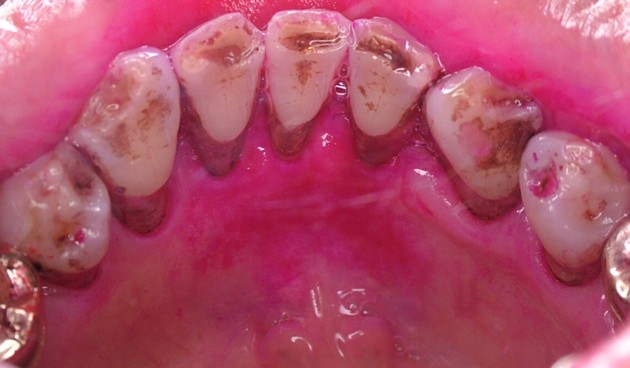

■ 色素沈着 ■

飲食物や嗜好品(コーヒーやお茶など)、体液中に含まれるメラニン色素などが歯面上に沈着したものです。直接的には為害作用はありませんが、審美性の問題や、あまり厚く沈着すると歯垢が付着しやすくなります。歯磨剤の的確な使用や歯科医師や歯科衛生士による歯冠研磨できれいになります。写真は下顎前歯の内側に見られる色素沈着です。